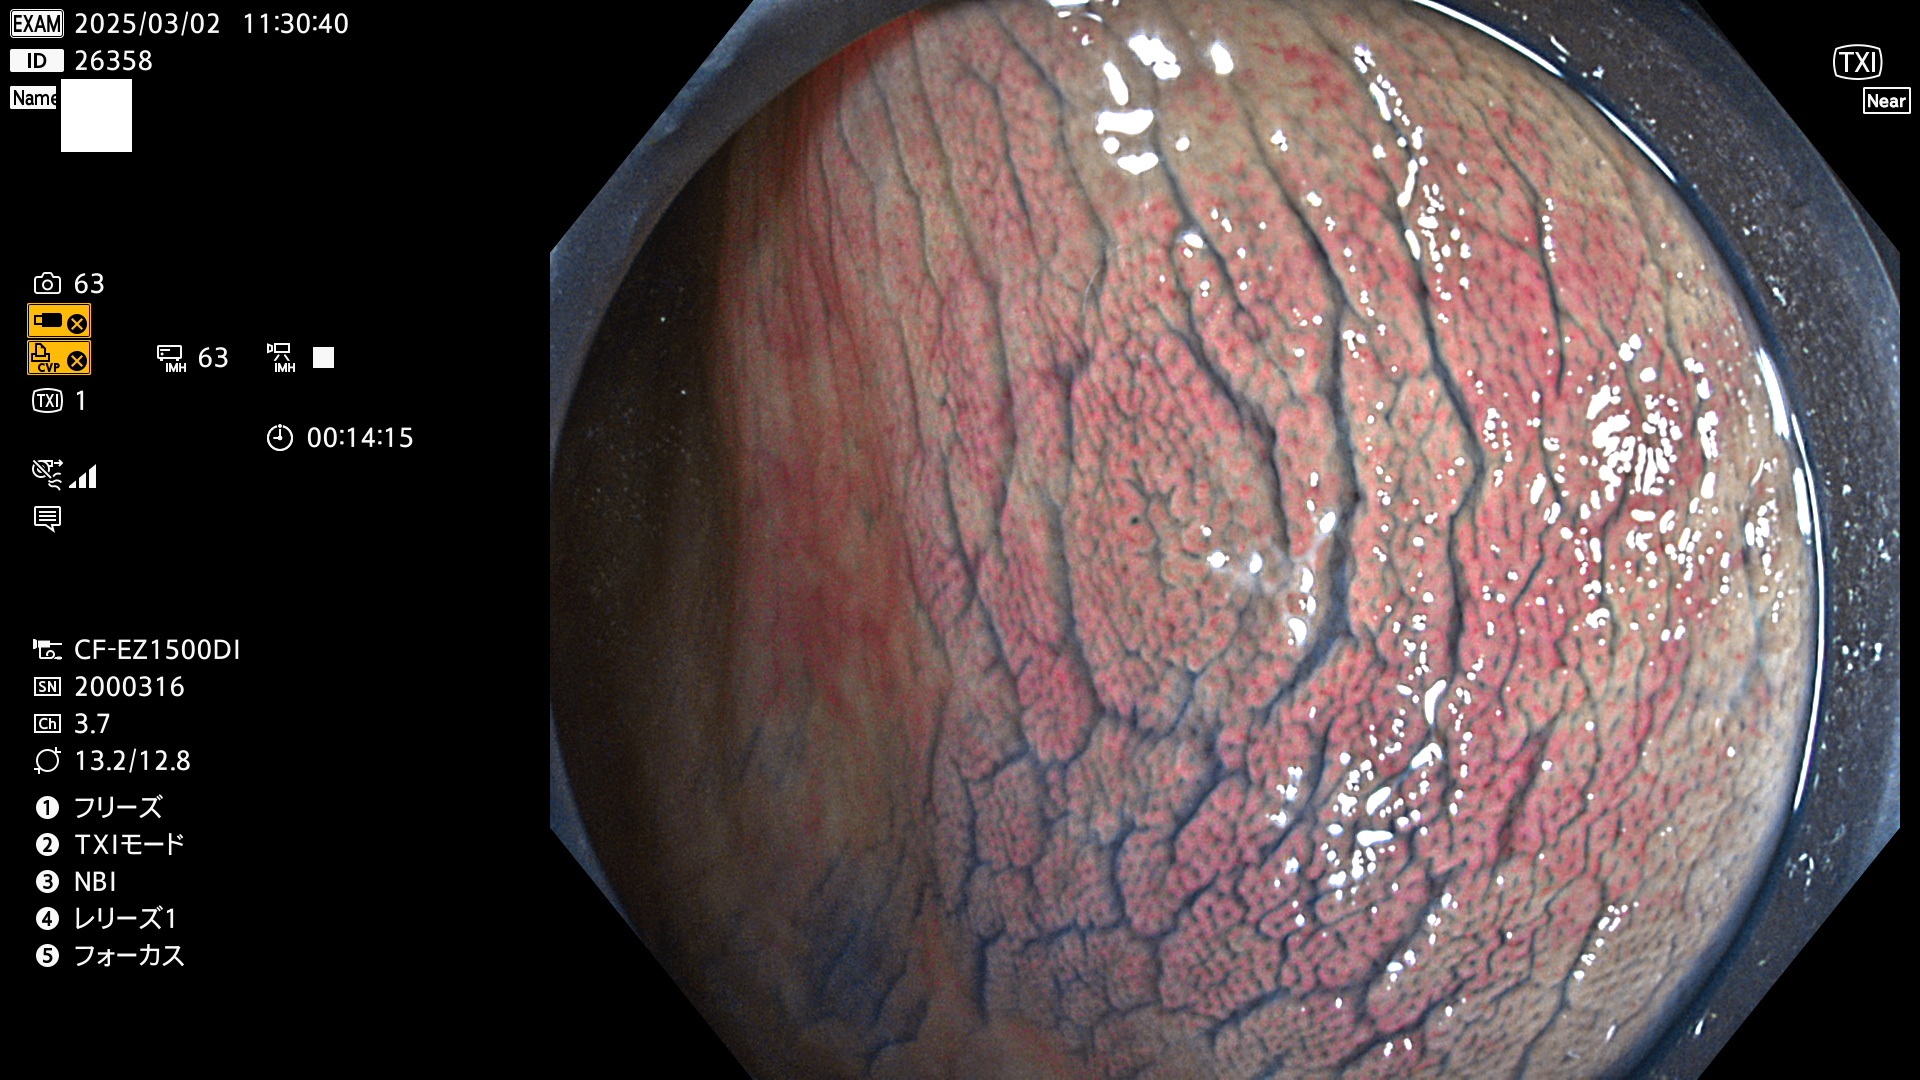

今週のUb、Uc型腺腫

完全に平坦な物をUb、陥凹している物をUcと呼びます。最も発見が難しく危険な病変です。

毎週の検査(木・金・土・日)に発見されたUb、Uc型・腺腫を、その週の日曜の夜にUPし1週間、提示します。

抽出の対象期間 2025年2月27日〜3月2日の4日間(48件の検査)9個 (9/48=19%)